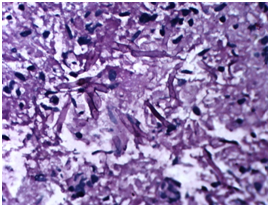

Patient was started on Amphotericin B after a test dose and a cumulative dose of 3grams was reached. A surgical intervention in terms of Tympanomastoidectomy with neck exploration was planned to decrease the disease load. However an extensive surgery was not possible because of poor surgical risk owing to multiple co-morbidities of uncontrolled hyperglycaemia, hypertension and deranged renal function tests. A canal wall down Mastoidectomy was done with exenteration of all the mastoid air cells including perisinus, perifacial, peri-labyrinthine and tip cells. The jugular fossa was cleared. Thick inspissated pus was evacuated from the mastoid cells. The postaural incision was extended on to the neck. Thick yellowish necrotic tissue involving upper part of sternocleidomastoid and posterior belly of Digastric muscle was seen Figure 5. The yellowish necrotic tissue was removed en block including the upper part of Sternocleidomastoid muscle reaching upto the stylomastoid foramen. Debridement was done and tissue taken for biopsy. Gomori Methamine Silver (GMS) staining of the biopsy material revealed fungal hyphae favouring Mucor species. Repeated cultures, Gram stain and Ziehl-Neelsen (ZN) stain for Acid fast bacilli (AFB) were negative (Figure 6).

Figure 6 Histopathological specimen showing septate acutely branching fungal hyphae suggestive of Mucor.

Diagnosis of Mucormycosis necessitates a high index of suspicion, as almost half of the cases are identified in post mortem studies.15,16 Diagnosis can be made by imaging studies and histopathological examination of the infected material. The fungus forms fluffy white, gray, or brownish colonies on Sabouraud dextrose agar within 1-7days. Direct microscopic examination can be done with 20% potassium hydroxide (KOH), Gomori's methenamine silver staining, hematoxilin and eosin staining, or periodic acid-Schiff staining (PAS). They are classically described as broad ribbon-like aseptate hyphae with right-angled branching. However, they are pauciseptate and the angle of branching can vary from 45° to 90°. Angioinvasion and tissue invasion are typical of this infection.